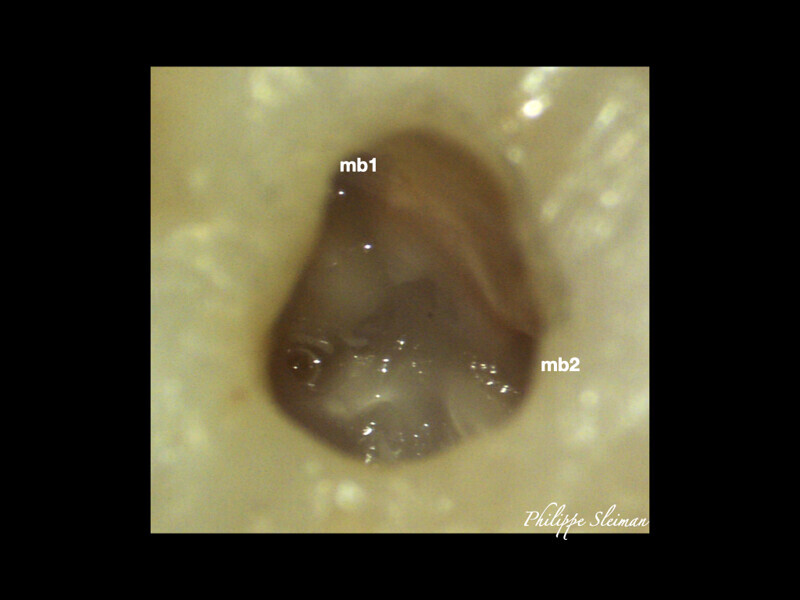

Clinical management of maxillary second molar root canal therapy in different anatomical situations